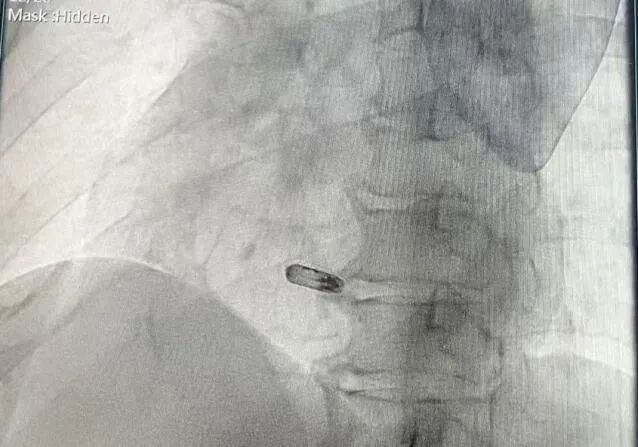

手术过程部分展示

释放无导线起搏器

术后右前影像

术后左前影像